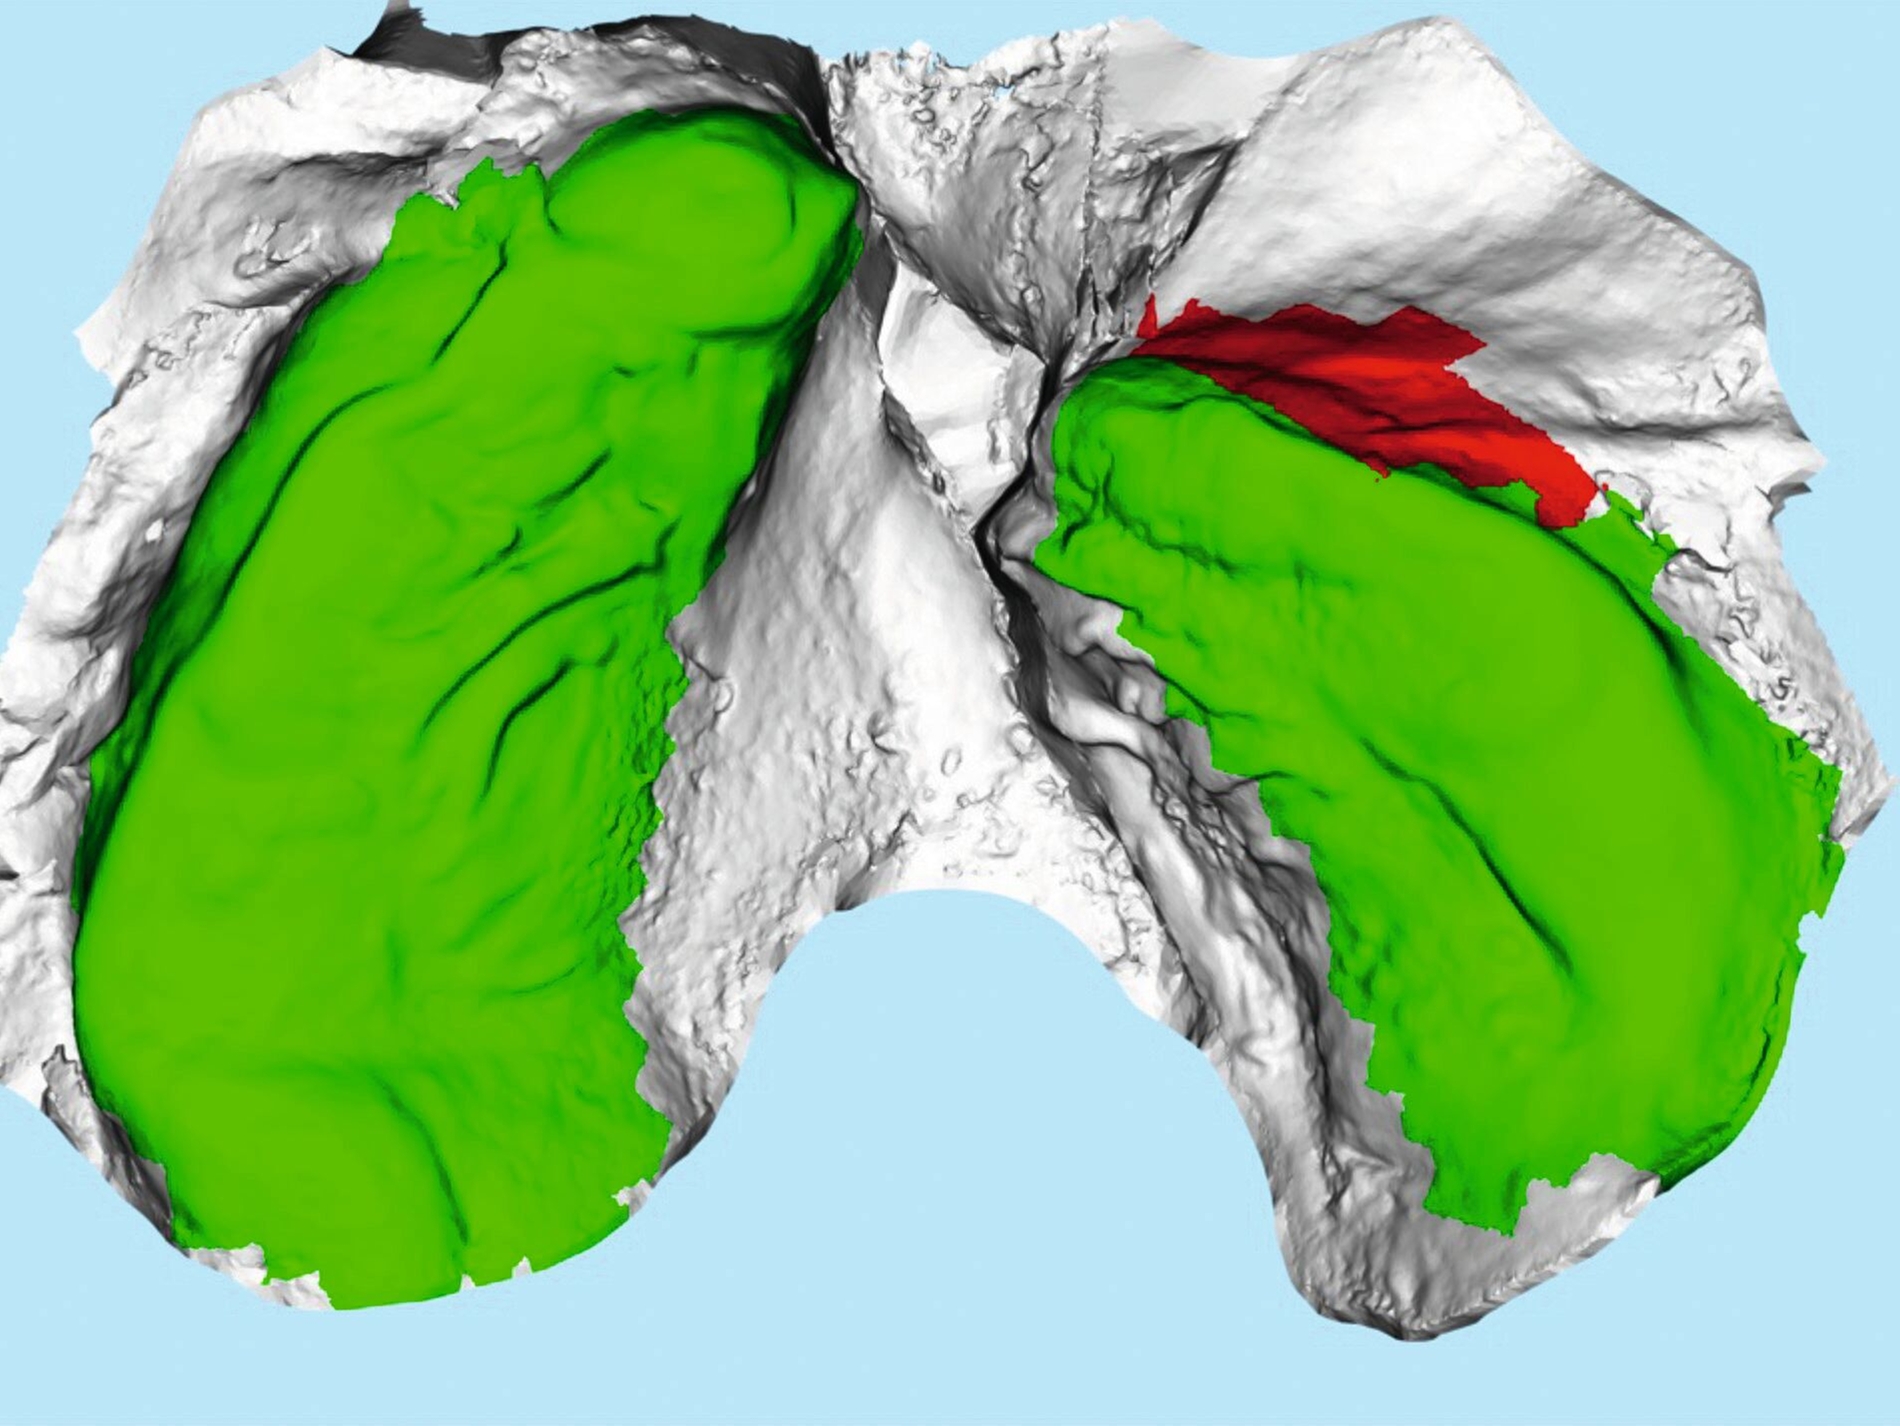

Weiter erlauben hochindividuelle 3-D-gedruckte Designs die Therapie von skelettalen Fehlständen, beispielsweise in der Therapie defizitärer Maxillae [Pasqua et al., 2022; Bazargani et al., 2023; Ludwig et al., 2024] oder im Rahmen der nonoperativen oder postoperativen Prognathie-Behandlung [Hodecker et al., 2023]. Auch die Umsetzung skelettal verankerter Apparaturen mittels nichtmetallischer 3-D-Druckmaterialien findet in einzelnen Fällen Anwendung (Abbildung 3b). Zum Einbringen der Miniimplantate eignen sich sogenannte 3-D-gedruckte „Insertions-Guides“, die nach vorheriger digitaler Planung der Miniimplantat-Position, eine hochgenaue Insertion ermöglichen [Wilmes et al., 2022; Wilmes et al., 2022]. Die virtuelle Planung der Minischraubeninsertion ermöglicht eine sichere und nachvollziehbare Evaluation sämtlicher relevanter Gewebe, um die ohnehin geringen Risiken weiter zu minimieren. Zusätzlich kann man die Biomechanik der digital geplanten kieferorthopädischen Apparatur ideal koordinieren und – wenn man möchte – die Minischrauben und die Apparatur in einer Sitzung einsetzen.